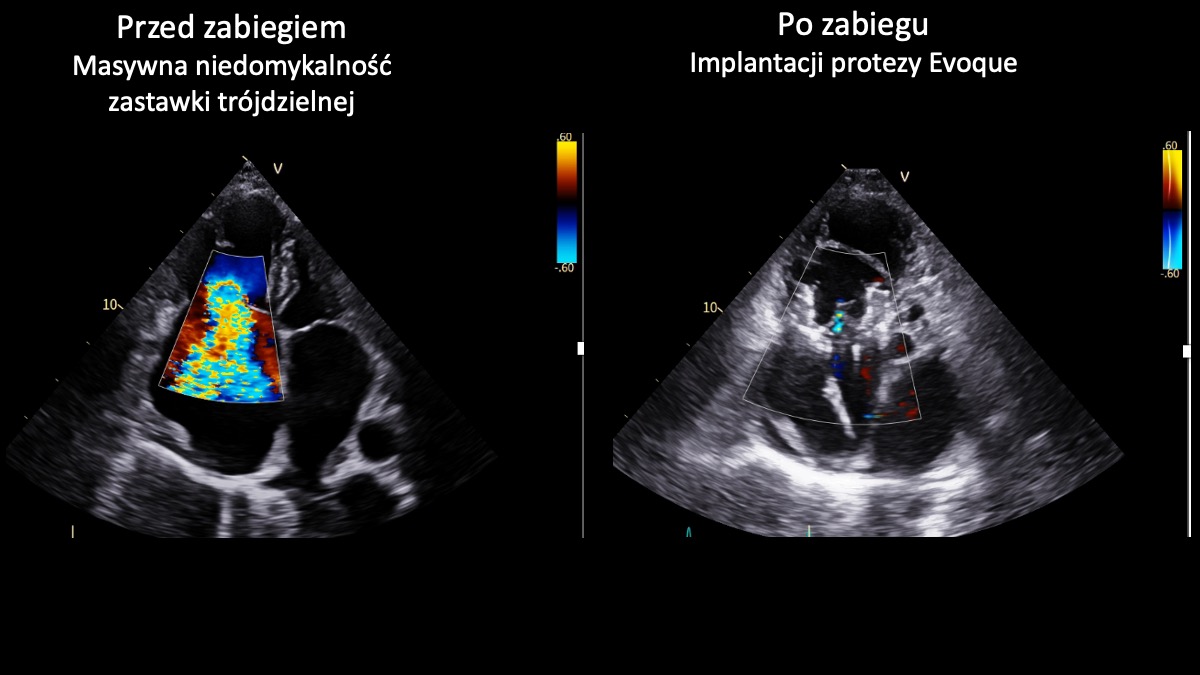

Zespół I Kliniki Kardiologii UCK GUMed, kierowanej przez prof. Marcina Gruchałę, z powodzeniem przeprowadził dwa nowatorskie zabiegi przezcewnikowej implantacji zastawki trójdzielnej Evoque z wykorzystaniem wizualizacji 3D. Te wyjątkowe – także w skali światowej – operacje są odpowiedzią na brak innej terapii dla pacjentów z niewydolnością serca spowodowanej masywną niedomykalnością zastawki trójdzielnej.

Zastawka trójdzielna znajduje się w prawej części serca i działa jak „zawór”, który zapewnia prawidłowy przepływ krwi w jednym kierunku. W przypadku niedomykalności nie zamyka się szczelnie, przez co część krwi cofa się, zamiast płynąć dalej. Masywna niedomykalność oznacza bardzo zaawansowaną postać tej wady – cofanie krwi jest znaczne, co prowadzi do przeciążenia serca i objawów takich jak: duszność, szybkie męczenie się czy obrzęki nóg. Nieleczona może prowadzić do poważnego pogorszenia jakości życia i niewydolności serca, a w konsekwencji – do śmierci.

Obie przeprowadzone implantacje zastawki trójdzielnej Evoque zakończyły się sukcesem. To ważny krok w rozwoju małoinwazyjnego leczenia pacjentów z zaawansowanymi wadami zastawkowymi. Dla chorych obciążonych bardzo wysokim ryzykiem operacyjnym i bez innych realnych możliwości leczenia to obecnie jedyna szansa na skuteczną terapię – podkreśla prof. Marcin Fijałkowski z I Katedry i Kliniki Kardiologii GUMed. – Zabiegi tego typu należą nadal do najbardziej zaawansowanych procedur w kardiologii interwencyjnej. Wykonując je w UCK, dołączyliśmy do wąskiego grona ośrodków europejskich oferujących pełne spektrum przezcewnikowego leczenia chorób strukturalnych serca, w tym wad zastawkowych – dodaje.

Zabiegi wykonano u dwóch 80-letnich pacjentek. Pierwszy z nich był monitorowany z wykorzystaniem nowoczesnego systemu echokardiograficznego GE HealthCare Vivid Pioneer, który umożliwia obrazowanie struktur serca w czasie rzeczywistym w technologii 3D. Drugą procedurę wspomagała sonda wewnątrzsercowa Philips VeriSight Pro 3D ICE, pozwalająca na wyjątkowo precyzyjną wizualizację serca podczas zabiegu. Zastosowanie tych technologii czyni przeprowadzone procedury nowatorskimi również w skali światowej. Tego typu zabiegi stanowią przyszłość kardiologii i wyznaczają kierunek dalszego rozwoju leczenia zaawansowanych chorób serca. Obie chore opuściły już szpital w stanie znacznej poprawy.